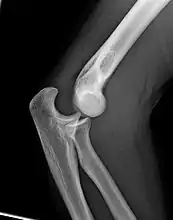

X-ray of ventral dislocation of the radial head. There is calcification of annular ligament, which can be seen as early as 2 weeks after injury.[29]

Elbow dislocations constitute 10% to 25% of all injuries to the elbow. The elbow is one of the most commonly dislocated joints in the body, with an average annual incidence of acute dislocation of 6 per 100,000 persons.[30] Among injuries to the upper extremity, dislocation of the elbow is second only to a dislocated shoulder. A full dislocation of the elbow will require expert medical attention to re-align, and recovery can take approximately 8–14 weeks.